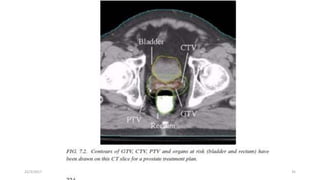

•Volume definition is a prerequisite for meaningful 3-D treatment

planning and for accurate dose reporting.

•ICRU reports No. 50 and 62 define and describe several target and critical

structure volumes that aid in the treatment planning process and that

provide a basis for comparison of treatment outcomes.

•The following volumes have been defined as principal volumes related to

3-D treatment planning: gross tumour volume (GTV), clinical target

volume (CTV), internal target volume (ITV) and planning target volume

(PTV)

2.3 Volume Definition

•The following are examples of the most common OARs that must be

considered:

1. Brain: lens of eye, optic chiasm, brain stem

2. Head & neck: lens of eye, parotid glands

3. Thorax: spinal cord, lungs

4. Abdomen: spinal cord, large bowel, small bowel, kidneys

5. Pelvis: bladder, rectum, femoral heads, large bowel, small bowel

2.3.6 Organs At Risk (Oar)